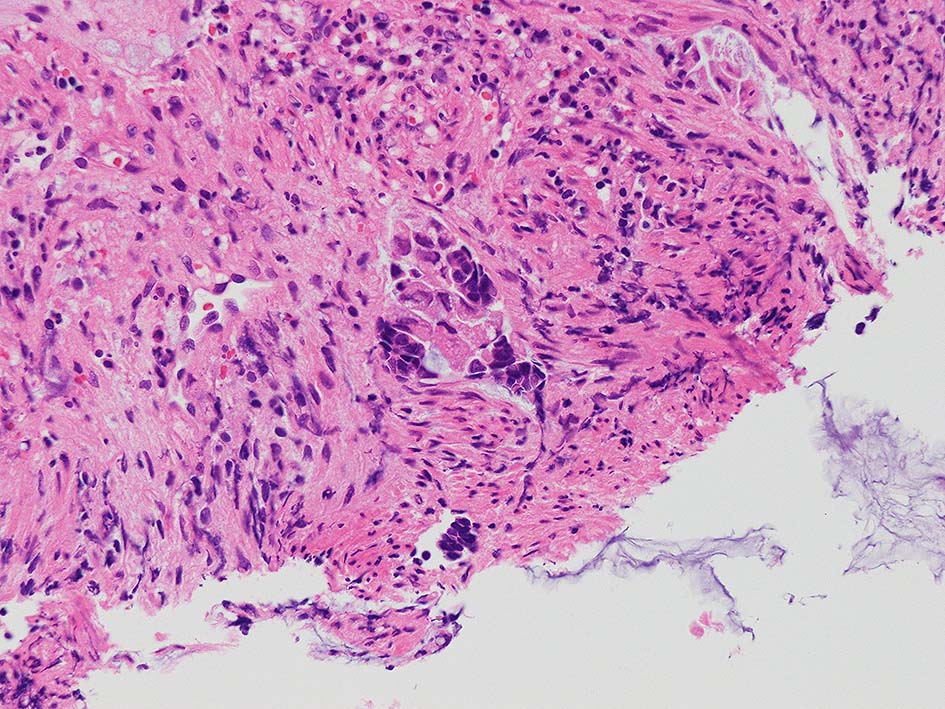

desmoplastic fibrosis, 粘液浸潤のみられる組織片にはsig, porのadenocarcinoma浸潤が確認される.